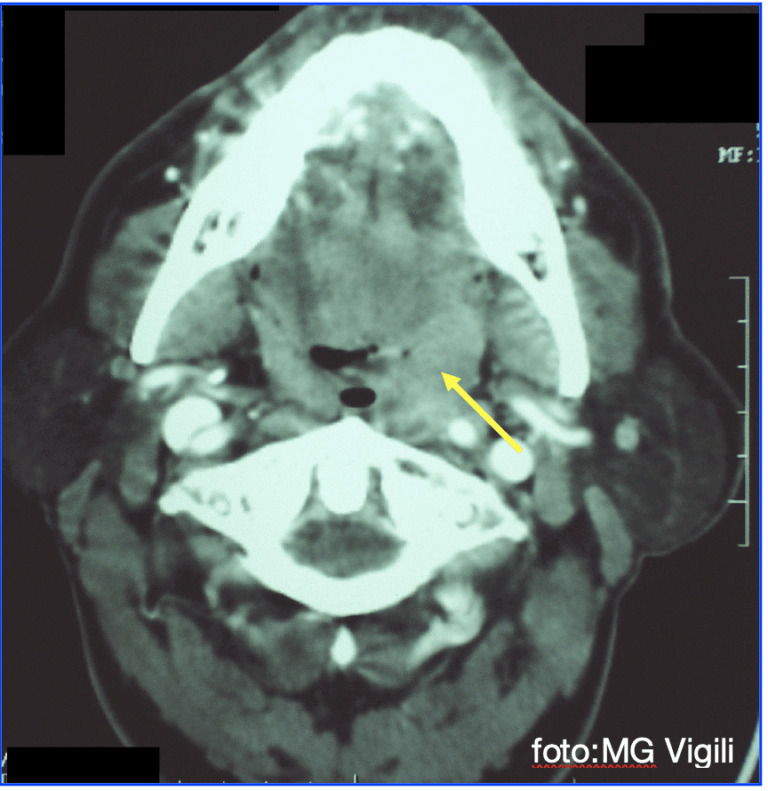

Maggior rischio di metastasi linfonodali nei giovani con carcinoma squamoso della tonsilla T1

Metastasi linfonodali controlaterali nei carcinomi squamosi della tonsilla